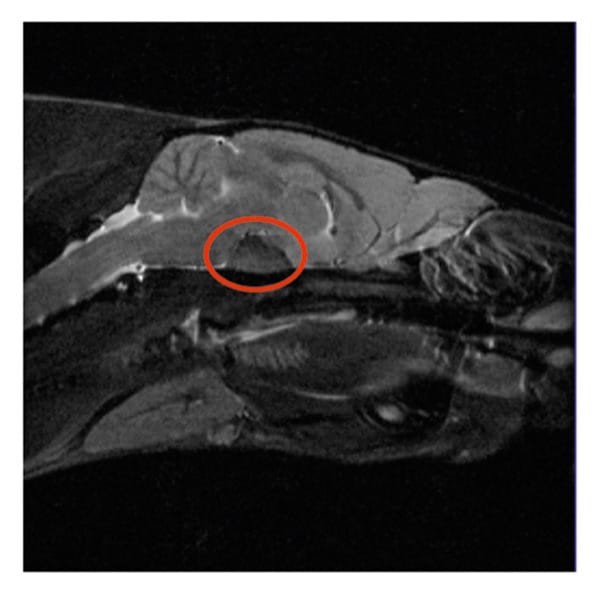

- МРТ та КТ з контрастом — найточніші методи для виявлення пухлини в мозку. Проводять їх тільки якщо це можливо та доцільно.

- УЗД черепа — новий метод, який добре допомагає бачити пухлини.